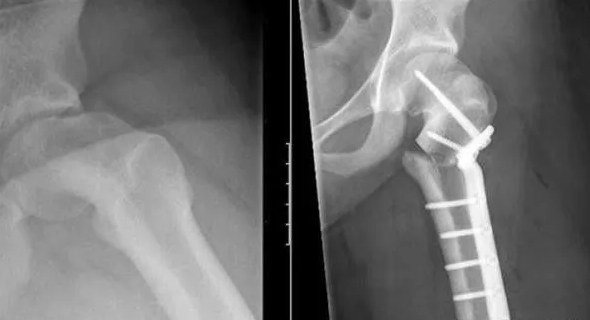

荷兰阿姆斯特丹的onze Lieve Vrouwe Gasthuis(OLVG)医院近日成功将一个3D打印的钛盘植入了一名13岁少女的臀部,完成了该国的例3D打印髋骨植入手术,而这名女孩也就此成为了该国体内拥有3D打印植入物的人。

据悉,为制造这个钛盘,医院先对女孩的髋关节做了3D扫描,然后将所得数据传送到了阿姆斯特丹Vrije大学医疗中心的3D创新实验室,接着,后者先用他们的3D打印机打印出了一个植入物的模型(为谨慎起见),后才用钛打印出了成品。